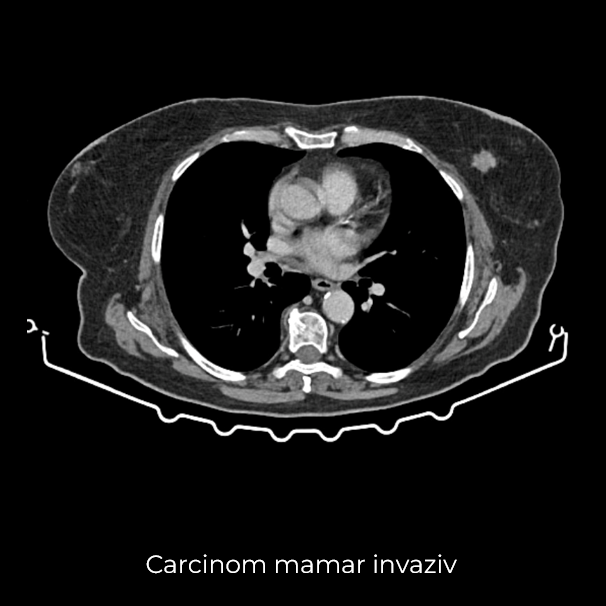

Uneori, o durere aparent banală ascunde în spate o realitate medicală mult mai serioasă. Așa s-a întâmplat și în cazul unei paciente de 63 de ani, care a ajuns la spital pentru dureri pelvine persistente. Investigația CT a schimbat însă complet perspectiva: au fost descoperite trei formațiuni tumorale în zone diferite ale corpului – o tumoră mamară stângă (carcinom mamar invaziv biopsiat), o tumoră pelvi-abdominală voluminoasă (tumoră ovariană) și o formațiune la nivelul peretelui posterior gastric (leiomiom gastric biopsiat).

- Mastectomie radicală stânga – incluzând identificarea și excizia ganglionului santinelă axilar (limfoscintigrafia efectuată în dimineața intervenției a indicat prezența unui singur ganglion santinelă)